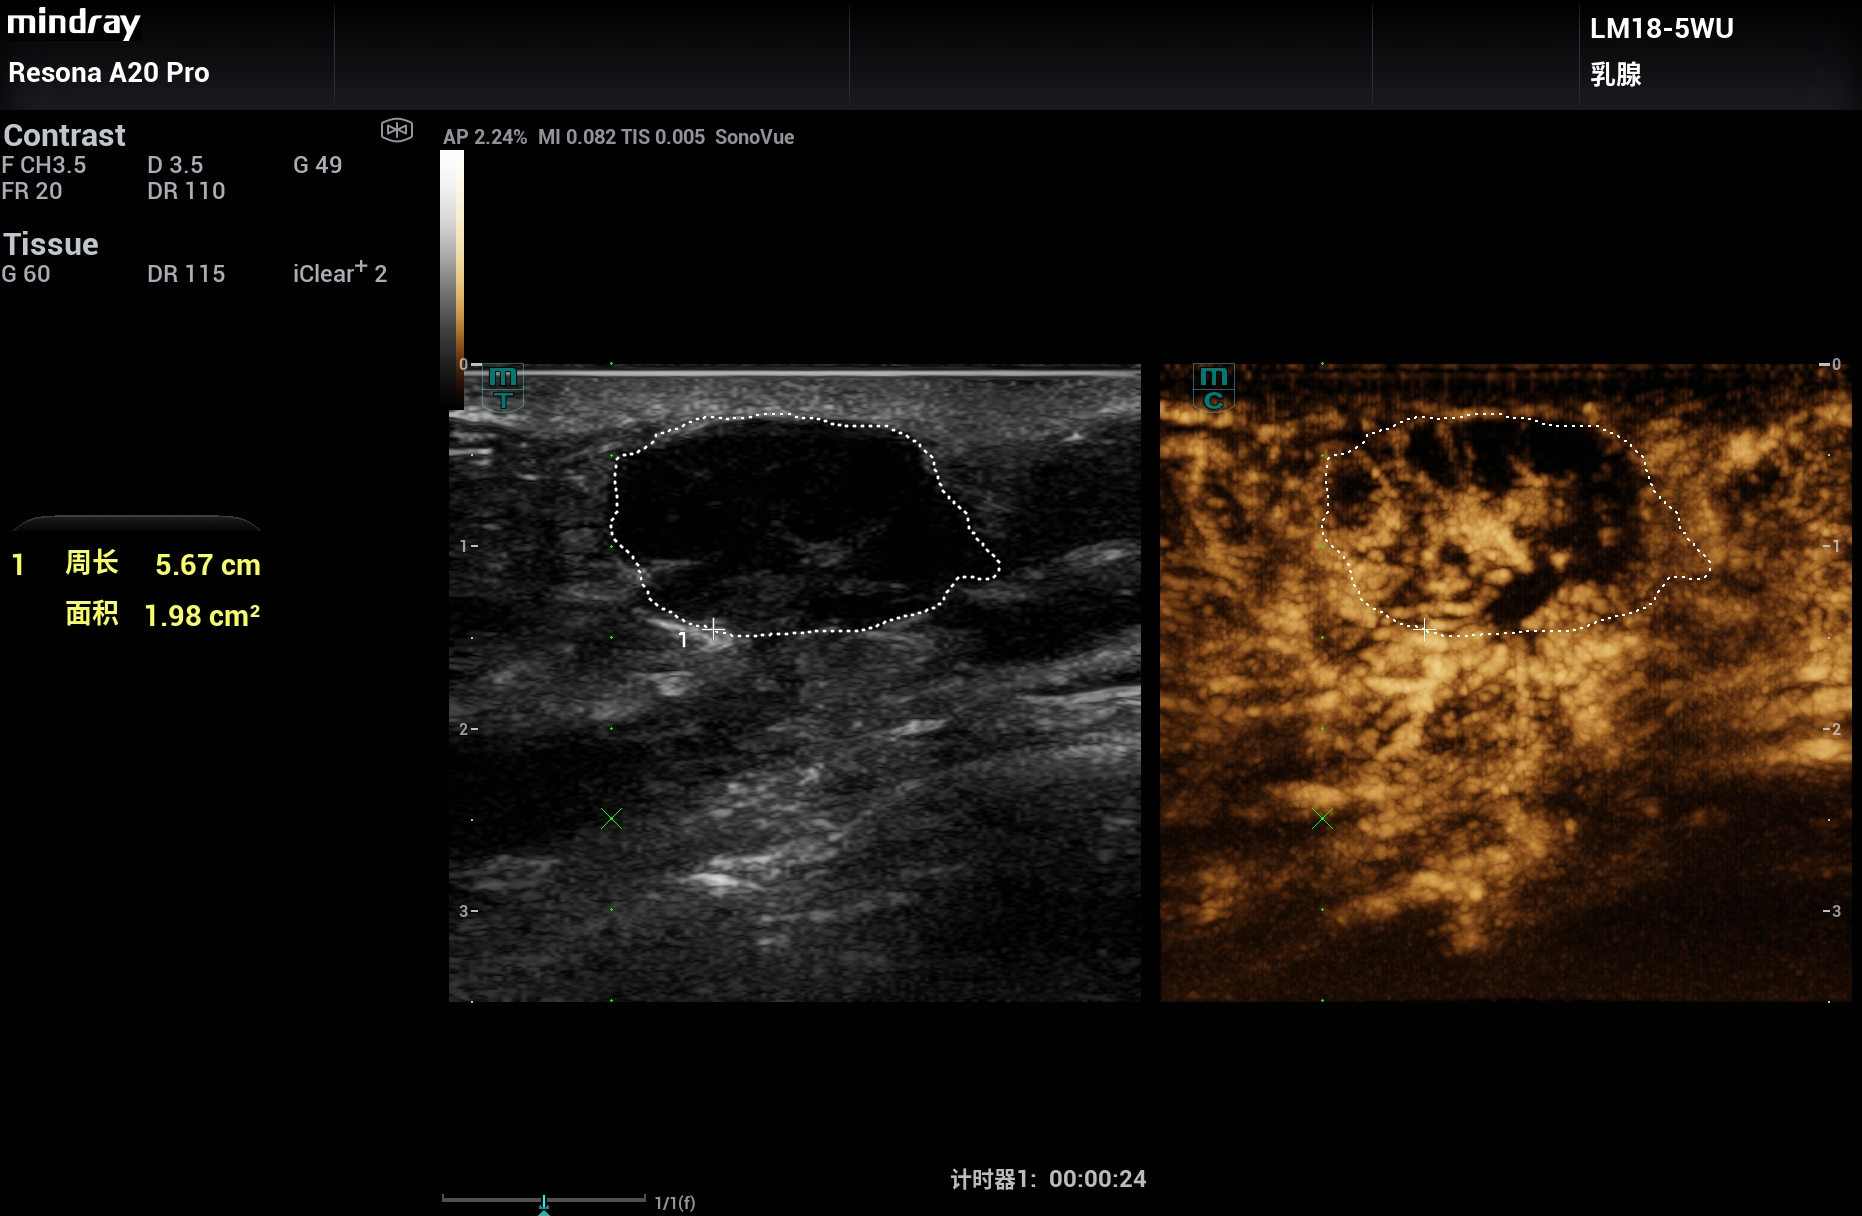

采用A20的超微血流UMA、睿瞳技术、弹性成像、造影和造影分析等高级技术。

其中睿瞳技术可以观察肿瘤周围边界的炎症高回声表现。

让乳腺疾病诊断更可信赖,更加精准。2025年11月。